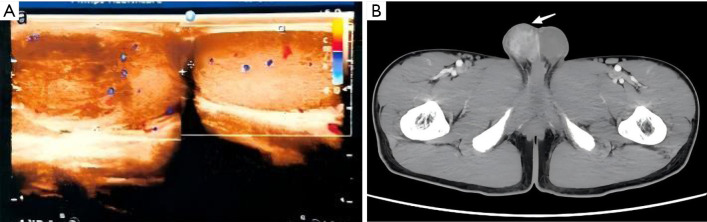

Case description: Clinical information for 11 patients with testicular abscesses who were diagnosed for surgical treatment in our hospital between 2006 and 2023 was retrospectively examined. Out of the eleven patients with nontuberculous testicular abscesses who had postoperative testicular pathology confirm the diagnosis, five had imaging-diagnosed testicular infarcts, two received orchiectomy due to misdiagnosis of testicular tumors, and one had an incorrect diagnosis of testicular torsion.